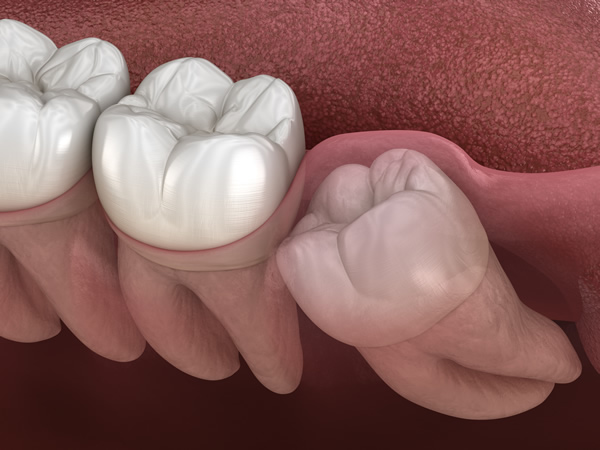

特に歯ぐきの中に埋まっている「埋伏歯(まいふくし)」の場合は、切開や骨の処置が必要となるなど、高度な技術と的確な判断が求められます。

横向きに生えている「水平埋伏歯」は、手前の歯を圧迫することで痛みや歯並びの乱れを引き起こし、虫歯や歯周病の原因になることがあります。

さらに、顎の骨や神経に近接しているケースも多く、抜歯には高度な技術と慎重な判断が求められます。